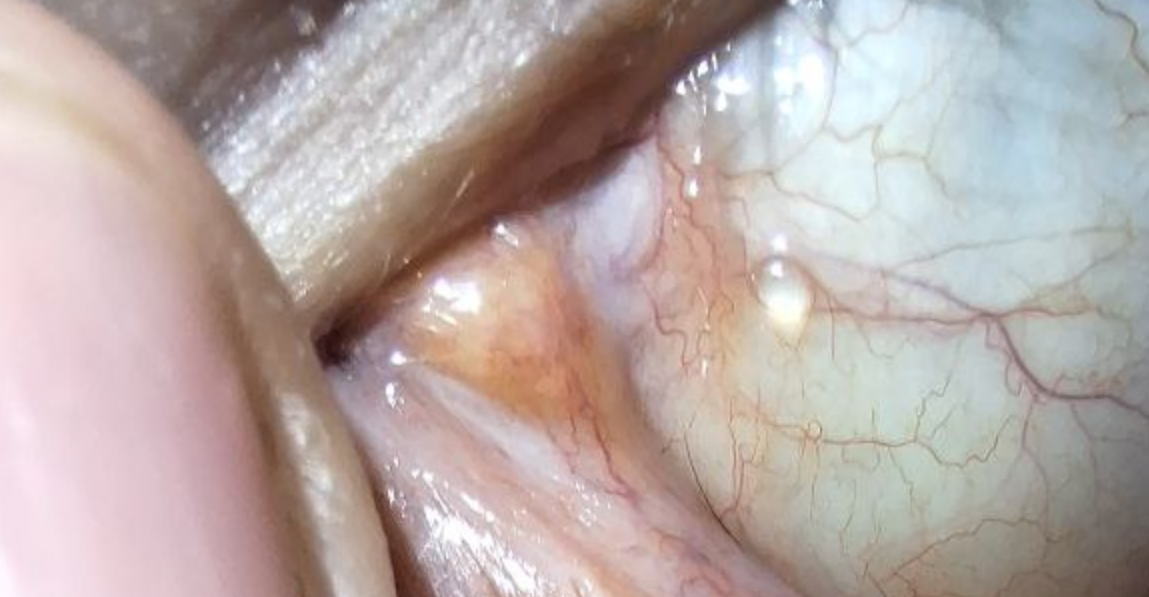

Здарова лепилы Аноним 08/12/25 Пнд 16:44:02 1651556 38

Год/полтора назад посетил весьма фешенебельное заведение с стариками и бомжами, поводил их по врачам, в поликлиники.

за месяц до события описанного выше, ещё от военкомата гонял по всяким злачным места типо дурдома и спид центра, и другой поликлиники, но там я отделался только бронхитом, и обструктивным кашлем.

так вот.

с тех самых пор сухость в глазах, колит их блять как будто я стоял на голове, а потом вдавил кулаками.

периодически заливает часть глаза бледным цветом маянеза со свеклой.

в гугле фоток нету, чтобы самодиагностировать эту ебанину,

и купить нужные капли / или показаний к пункции, т.к. не ясно на сколько глубоко под слизитой это образование.

+ моё нижнее веко стало морщинистым, потемнело, и имеет дерматитную текстуру.

По анамнезу глаза - потеря зрения из-за травмы головы в лет 5, частичное отмирание нерва.

в 17~ было кровоизлияние, залило весь белок как у гуля 1000-7, нижнего и верхнего века, видимо кривая пункция пазух.

всё это было после выписки от геморальных и инфекционных фронтита и синусита.

спасайте бляди, к вам на приём я не пойду, потому что вы хуесосы меня опять на опыты студентам сдадите.

мимо жертва карательной медицины 90-ых.

Аноним 08/12/25 Пнд 17:12:22 1651558 39

image.png 404Кб, 900x400

900x400

>>1651556

у одного из лепил (офтальмолога) были такие глаза,

но она вроде меня не трогала.

но эта хуйня могла передаться через пациента?

Аноним 08/12/25 Пнд 17:16:30 1651560 40

блять сука, видимо киста конъюнктивы от хронической инфекции

+ рецидивное заражение.

ебал в рот эту страну.